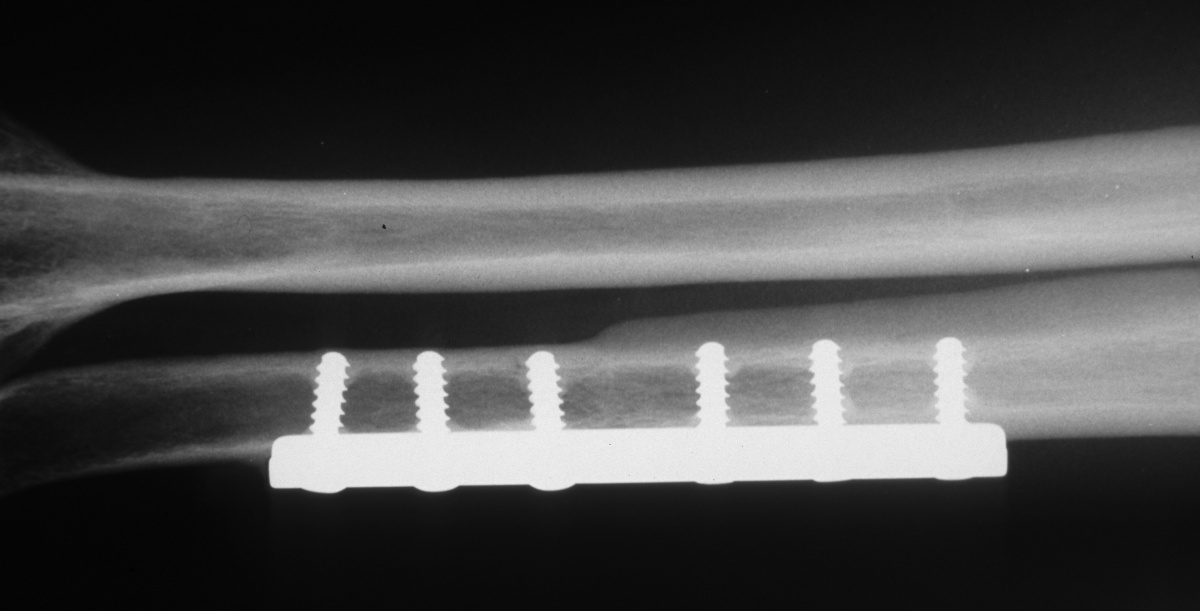

| After release of both

pronators from the radius and release of the distal half of the

interosseous membrane, passive supination was unchanged. A 60 degree

ulnar supination and 2 mm shortening osteotomy was performed,

with nearly 60 degrees improvement of supination intraoperatively. |

| Ulnar styloid position on a

forearm AP radiograph demonstrates the degree of rotation |